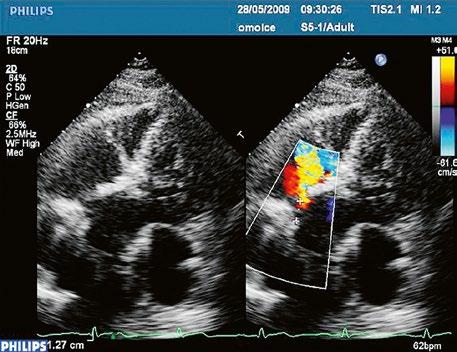

z Defekt síňového septa typu sinus venosus superior: 9 %, v místě vústění horní duté žíly (HDŽ), která na defekt nasedá, téměř vždy je spojen s parciálním anomálním návratem pravostranných plicních žil do HDŽ nebo do pravé síně (kap. 45.18 Anomální návrat plicních žil (Obr. 45.3, Obr. 45.4, Video 45.3, Video 45.4).

Obr. 45.3 Defekt septa síní typu sinus venosus superior, TEE nad úrovní aortální chlopně, defekt je v horní části septa označen křížky

AO – aorta, LS – levá síň, PS – pravá síň

Obr. 45.5 TEE, longitudinální projekce, dva menší defekty typu sinus venosus inferior v dolní části síňového septa s levopravým zkratem označeny bílou šipkou, v místě vústění dolní duté žíly (DDŽ) do pravé síně (PS) LS – levá síň

Obr. 45.4 Defekt typu sinus venosus superior s levopravým zkratem v barevném dopplerovském mapování. TEE v longitudinální projekci, defekt se nachází v horní části septa, je označen žlutou šipkou, na něj nasedá horní dutá žíla (HDŽ)

AP – plicnice, LS – levá síň, PS – pravá síň

Obr. 45.6 TEE, longitudinální projekce, menší defekt typu sinus venosus inferior (12 mm) označen křížky. (Stejná pacientka jako na obrázku 45.7.)

DDŽ – dolní dutá žíla, LS – levá síň, PS – pravá síň

Obr. 45.7 TEE longitudinální projekce, defekt typu sinus venosus inferior s menším levopravým zkratem v barevném dopplerovském mapování (stejná pacientka jako na obrázku 45.6)

Video 45.3 TTE, čtyřdutinová apikální projekce, v barevném dopplerovském mapování patrný levopravý zkrat defektem typu sinus venosus superior

Video 45.4 TEE, longitunální projekce, v barevném mapování je patrný levopravý zkrat v horní části síňového septa v místě nasedání horní duté žíly na defekt (Obr. 45.4)